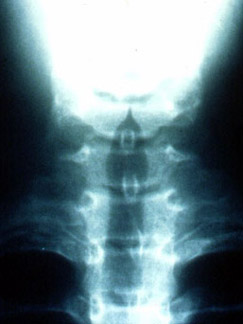

AP projection illustrates a normal tracheal air column.